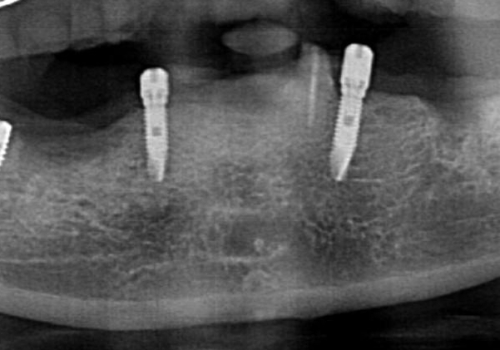

入れ歯の下部にインプラントを4本埋入し、マグネットアバットメントを装着することでしっかりと咬むことのできるインプラントオーバーデンチャーによる補綴を計画します。

- 44万円(インプラント×4・マグネットアバットメント×4・金属床義歯)費用は治療当時の料金となります

インプラントで支えない総義歯よりも、マグネット付きのインプラントで支えることでかたつきのなくしっかりと咬める入れ歯治療を行うことができました。